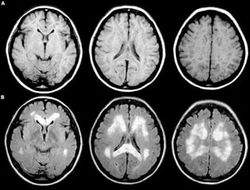

После нескольких смертей вследствие кровоизлияний в мозг по итогам боёв, власти Филиппин решили всерьёз взяться за ужесточение правил медицинского осмотра, на котором врачи решают — выдавать (или оставлять) боксёру лицензию, либо отобрать.

Таким образом, каждый седьмой боксёр страны (всего на Филиппинах 1054 легальных боксёров) подделал документы, чтобы иметь возможность выступать. Большинство из мошенников сделали это по причине бедности: не каждый спортсмен в стране может заплатить от $150 до $500 за КТ- или МРТ-обследование.